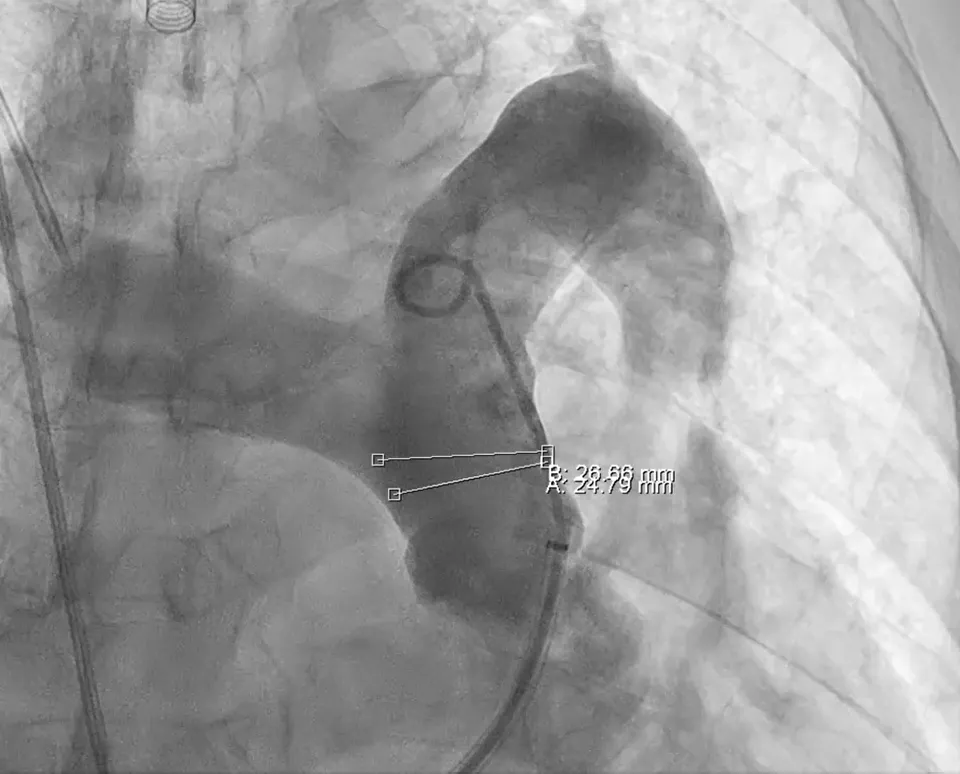

PADN 手术过程患者 PADN 手术前行右心导管检查示 RAP 16mmHg,PAP 51/20/30mmHg,PAWP 21mmHg,PVR 2.42wood,测量肺动脉主干直径约 26mm。根据消融导管圈径:肺动脉主干直径 = 1:1.1-1.2,选择 30mmPADN 导管。术者通过导管贴靠三个目标靶点进行消融,消融过程顺利。

PADN术中造影和导管消融图(见下图):

LAO0°+CRA20°造影体位测得主肺动脉直径约26mm